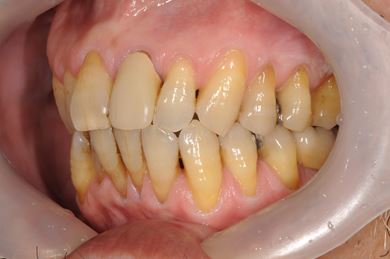

| 性別/年齢 | 男性 / 60歳 | ||||||||||||||||||||||||||||||||

| 主訴 | 右下奥歯の治療相談。(痛み・ぐらつき・物がかめない) | ||||||||||||||||||||||||||||||||

| 治療方針 | 左下奥の欠損部分をインプラント治療にて、機能的・審美的に回復を行う。 | ||||||||||||||||||||||||||||||||

| 治療内容 | インプラント2本、メタルボンドセラミッククラウン2本 | ||||||||||||||||||||||||||||||||

| 総治療費 | 680,610円 | ||||||||||||||||||||||||||||||||

| 治療期間 | 7ヶ月 |